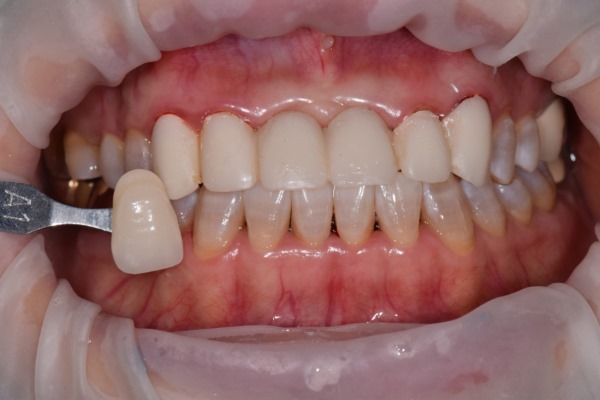

윗니 치아 3번부터 - 3번까지 6개 치아를 브릿지(연결되어 있는 크라운)로 예전에 치료 경험 있는 환자분이 오셨어요. 위 환자분께서는 안쪽엔 금속(메탈)을 포함하고 겉면은 치아색인 PFM 크라운을 사용 중이셨어요.

앞니에 이러한 PFM을 사용 시 치아와 잇몸라인 쪽에 지금처럼 검은 선이 생기게 되죠. 또한 치아 색도 원래의 자가치아보다 색감이 어둡게 나올 수밖에 없습니다. (자가 치아의 색은 약간의 투명감을 띄고 있죠)

일단 기존의 크라운을 제거한 후 잇몸라인을 정리해야 할 것 같죠? 잇몸성형을 함께 진행 한 후

새로운 크라운의 색을 결정해야 합니다. 치아색은 새로 하는 6개 치아만은 생각해선 안되겠죠. 주변 치아와의 색의 조합, 크기,모양의 조합도 생각해야 합니다.

위 사진은 잇.몸.성.형 후 올세라믹 크라운 세팅하셨네요.

치아의 투명도, 크기 ,모양, 잇몸라인 꽤 괜찮아 보입니다. 환자분도 만족하셨고요.